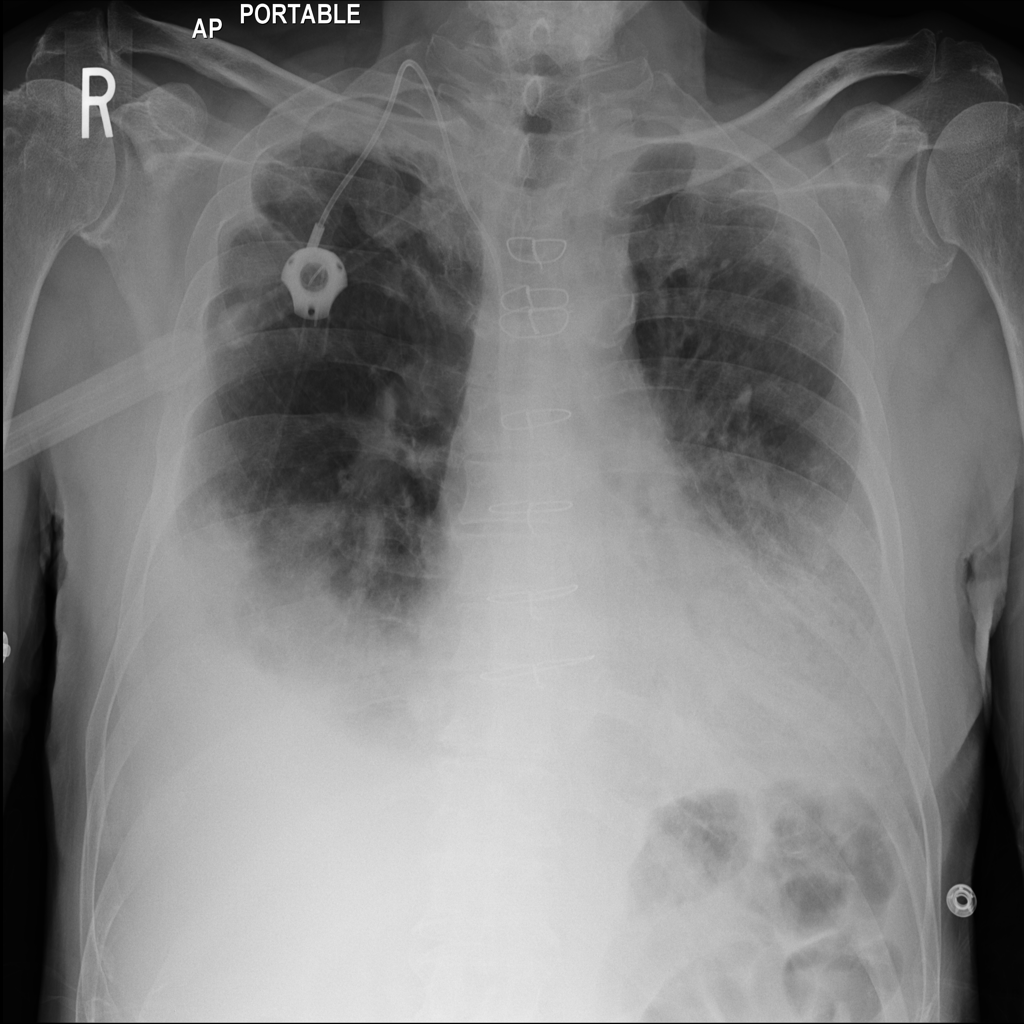

PAT-40F9 · IMG-004Effusion

PAT-40F9 · IMG-004

PA